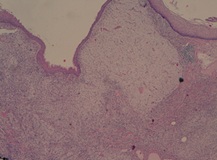

A CT scan of the neck revealed thickening of the cervical esophagus in the absence of other pathological finding (figure 1).

Figure 1: CT image of the esophageal polyp